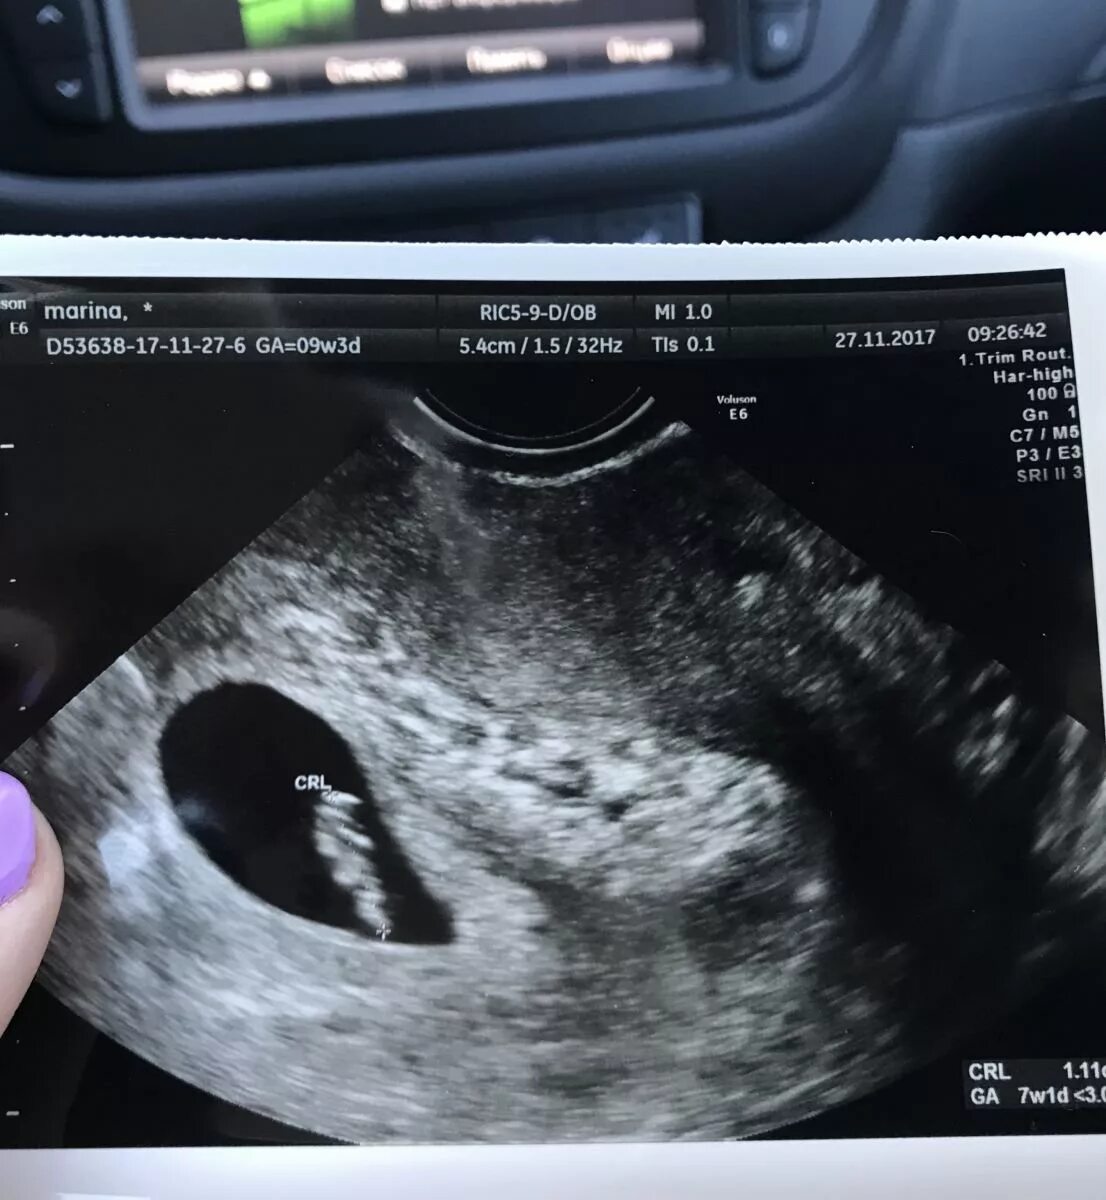

Эмбрион 7 дня форум